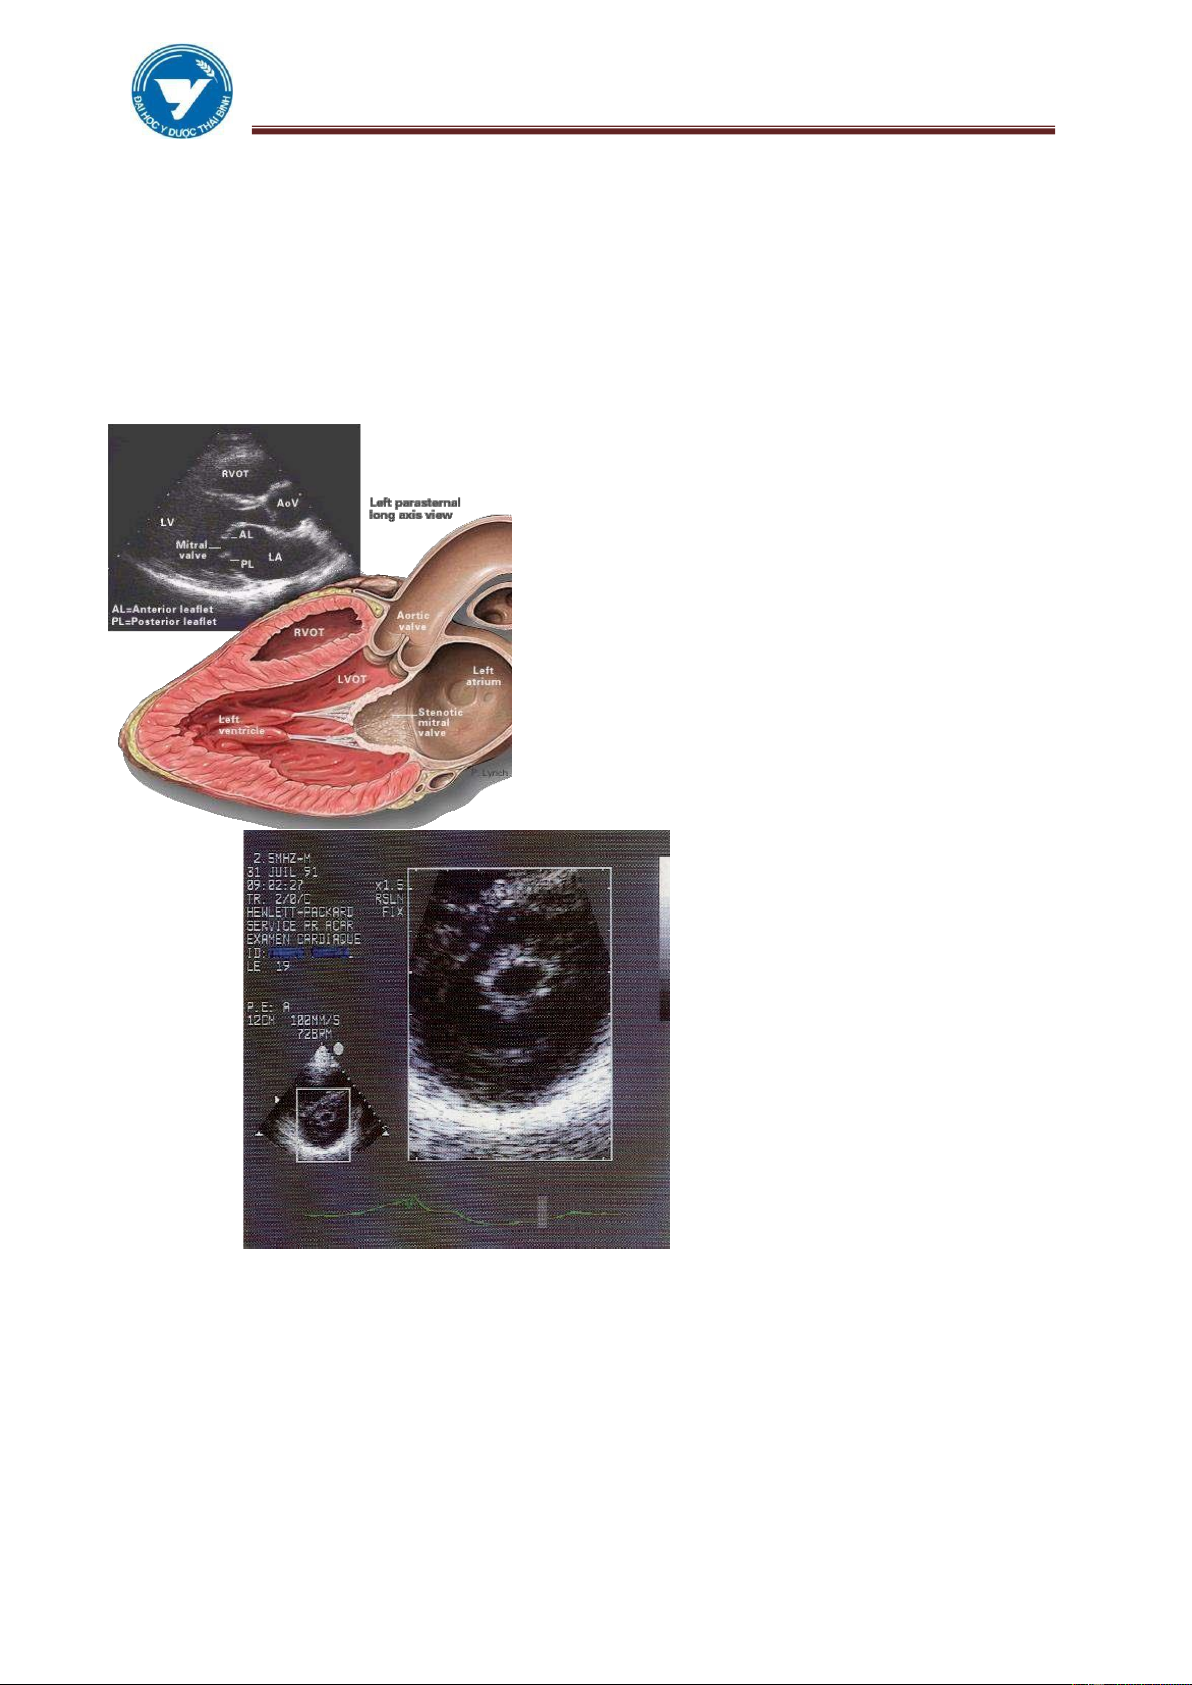

2.1. Siêu âm tim

Là 1 trong những kỹ thuật hình ảnh chủ lực ối với hệ tuần hoàn hiện nay,

với tất cả các kiểu (Mode) 2D, TM, ặc biệt là SÂ Doppler xung, Doppler liên tục,

Doppler màu ã ánh giá ược hình thái và chức năng của tim khá ầy ủ.

Một số các kích thước của buồng tim, van trên SÂ:

Kích thước của thất trái trên SÂ: LVPW = 6-12mm; buồng thất trái: LVED =

39-56 mm. Vách liên thất IVS = 6-12mm

Kích thước của thất phải trên SÂ: RVED = < 30mm Chỉ số co hồi thất trái:

FS (Fractional shortening) = 0,25-0,42 Kích thước của lổ van 2 lá >16mm.

Kích thước của ĐMC: 20-37mm, ĐMP trên SÂ. lOMoAR cPSD| 22014077 lOMoAR cPSD| 45148588

3.2. Hình ảnh siêu âm

Hẹp van 2 lá: Thấy trực tiếp kích thước của lỗ van , xác ịnh tính mềm

mại của các van hay thâm nhiễm, sùi. Thấy nhĩ trái lớn hơn rõ, có thể thấy

ược cục máu ông ở trong buồng tim.

Hở van 2 lá ơn thuần: triệu chứng trực tiếp áng tin cậy, có thể thấy ược dây

chằng (tổ chức dưới van) bị ứt, tăng ộng thất trái, tăng thể tích thất trái.